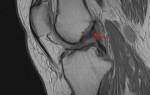

Разрыв связок приводит к резкому ограничению функции сустава и болезненности при пальпации. При осмотре врач выявляет кровоизлияние в области травмы, припухлость и сглаженность силуэта поврежденного сустава. В отличие от перелома, при растяжении и разрыве связок деформация конечности отсутствует. Если боль и затруднения в движении суставом сохраняются более 2–3 дней, следует подозревать перелом или серьезное повреждение связок. Врач может назначить рентген для исключения перелома.

При растяжении в крупном суставе возможно повреждение внутреннего связочного аппарата, что проявляется резкой болью, невозможностью разгибания сустава, а также щелчками или хрустом в суставе.